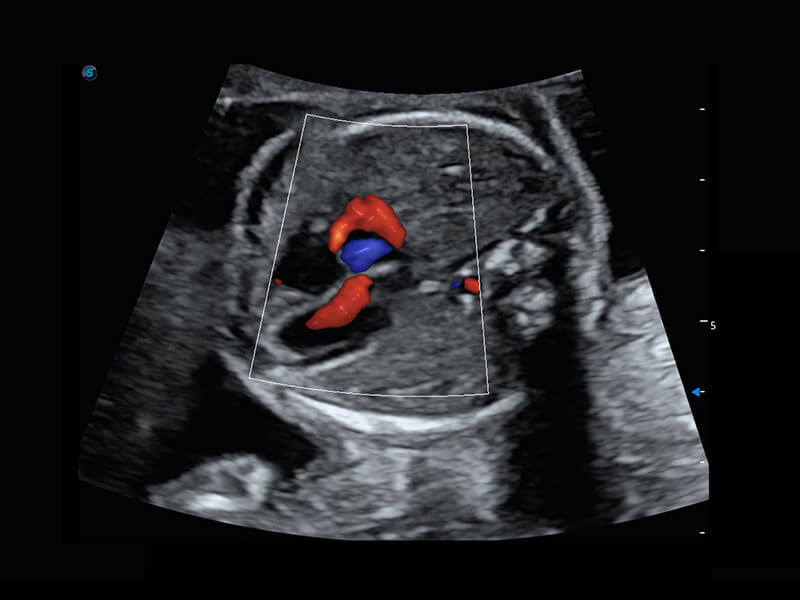

新生儿肝血管癌

新生儿心脏